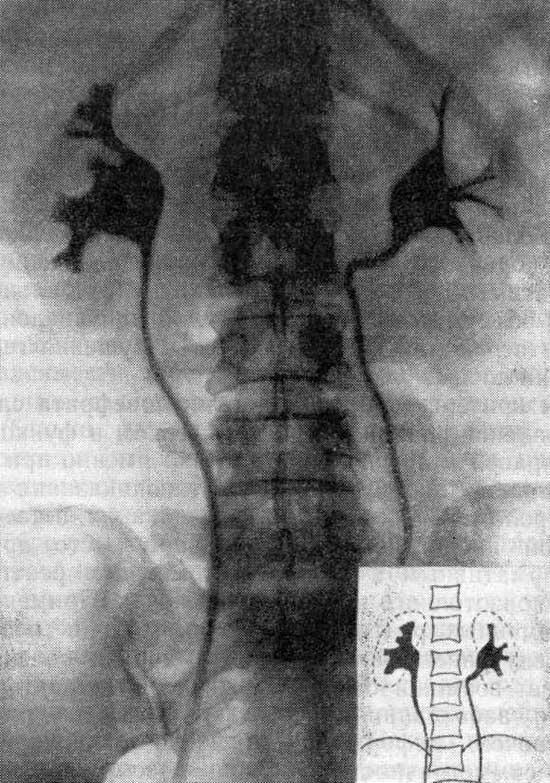

Медицинские изображения: Обзорная рентгенография урография

Раздел: Фокус на знании